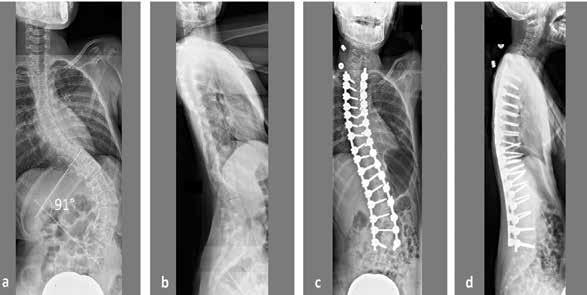

Scoliosis, an often hereditary spinal condition that can develop in infancy or early childhood, is an abnormal lateral curvature of the spine causing an irregular S-or C-shaped curve, that can cause discomfort and challenges, and may require treatment.

Scoliosis affects 2-3% of the population accounting for roughly six to nine million people across the United States, with “the primary age of onset for scoliosis is 10-15 years old, occurring equally among both genders,” according to the American Association of Neurological Surgeons.

Luke Stikeleather, founder, president, and chief orthotist with the National Scoliosis Center, works with a plethora of children facing scoliosis at both his Baltimore and Fairfax County office locations.

As an orthotist, Stikeleather is trained in fitting and creating braces and splints. He spoke with The Washington Informer to share expert facts about scoliosis and clarify any misconceptions.

Did You Know the Varying Degrees of Scoliosis?

“Scoliosis can be a small curve. It can be a single curve, a double curve. It can be higher in the spine or lower in the spine. So it depends on the [individual] and how that person is growing.

It’s often driven by growth. So the occurrence is in about 3% of the population of that a small minority will end up having to have it treated. And we don’t treat curves, generally speaking, below 20 degrees, so there needs to be a size that the physician deems appropriate for bracing.”

Between 20 and 50 degrees is the range that’s often suggested for bracing. And above 50, surgeons start to talk about the need, potentially, for a surgical intervention for a fusion of the spine.”

So, identifying it is the first line of priority and defense, and if you can identify a small curve, treat a small curve, and keep it at those smaller values, then you’ve avoided a big problem in the future.”